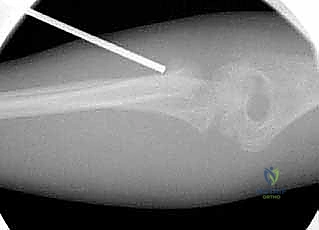

1. الرد المغلق والتثبيت عبر الجلد (CRPP - Closed Reduction and Percutaneous Pinning)

هذه هي التقنية السائدة والمفضلة عالمياً لعلاج كسور عنق الكعبرة لدى الأطفال (تقنية ميتازو Métaizeau Technique). وهي تقنية طفيفة التوغل لا تتطلب شقاً جراحياً كبيراً، مما يحافظ على الأنسجة المحيطة ويقلل من خطر الندبات وتيبس المفصل.

بما أن كسور عنق الكعبرة